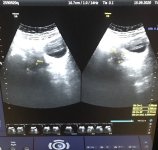

وبعد ظهور النتيجه اتضح ان لدي كيس على المبيض الايمن حجمه ٢ سم او اكبر قليلا ووصفت لي دواء primolt n لتنزيل الدوره اتصلت بي اليوم لتخبرني ايضا بنتايج التحاليل الاخرى وقالت ان هرمون الحليب مرتفع عندي كثيرا ولم تخبرني ما هي النسبه واوصتني باخذ علاج dostinex واذهب لها اليوم ١١ من الدوره واخبرتني ان اتي لها خامس يوم من الدوره لترى هل الموجود على المبيض كيس دموي او بطانة رحم مهاجره السوال

مرفق صورة السونار للمبيض

اهلا بحضرتك. وصفك يرفع احتماليه وجود مشكله بطانه الرحم المهاجره فهي تسبب تأخر الحمل والآلام الشديده مع الدوره، ايضا يصاحبها ارتفاع في نسبه هرمون الحليب في الدم ؛ اذا سيكون العلاج هو لمشكله بطانه الرحم المهاجره للمساعده علي حدوث حمل. وليس علاجا لارتفاع هرمون الحليب بشكل منفصل، سيبدأ الطبيب بتقييم كل العوامل اللازمه لحدوث الحمل ابتداءا بتحليل الزوج مرورا بالهرمونات والاطمئنان علي حدوث التبويض واشعه الصبغه للرحم وتقييم سلامه انبوبتي فالوب وانتهاءا بمنظار البطن الذي يؤكد تشخيص بطانه الرحم المهاجره. ويحدد درجه الشده وممكن ان يبدأ العلاج بالمنظار ،وبعد تقييم حضرتك في ضوء كل ماسبق سيضع الطبيب خطه العلاج المناسب لحضرتك علاج دوائي مع تنشيط للتبريد وتلقيح صناعي. اذا لم تحدث استجابه خلال ٦شهور ممكن اللجوء لاطفال الانابيب. العلاج محتاج بعض الصبر والتعاون. بالنسبه لصوره السونار المرفقه فهي ليست واضحه ممكن تجمع دموي صغير بسبب بطانه الرحم المهاجره فلن تضيف شيئا